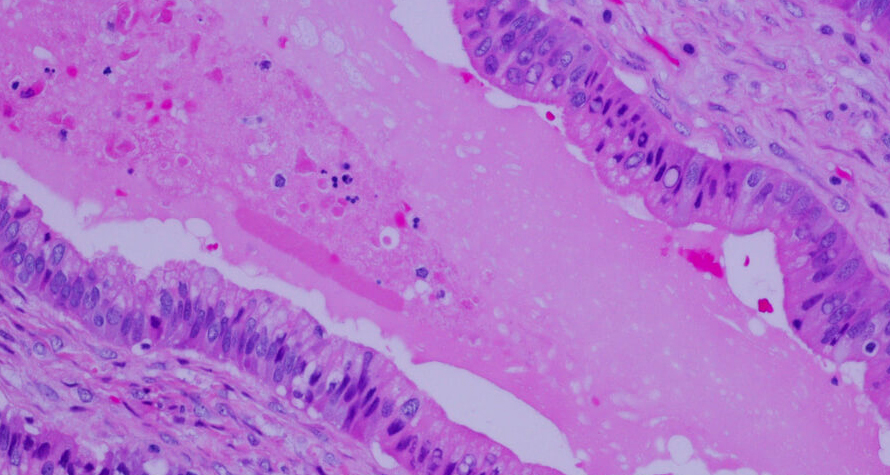

Image Description